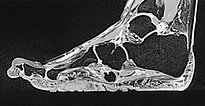

In der sagittalen , T1-gewichteten, fettunterdrückten MRT (wieder gleiche Schichtebene) findet sich ein geringes, relativ homogenes Enhancement des Nävus.